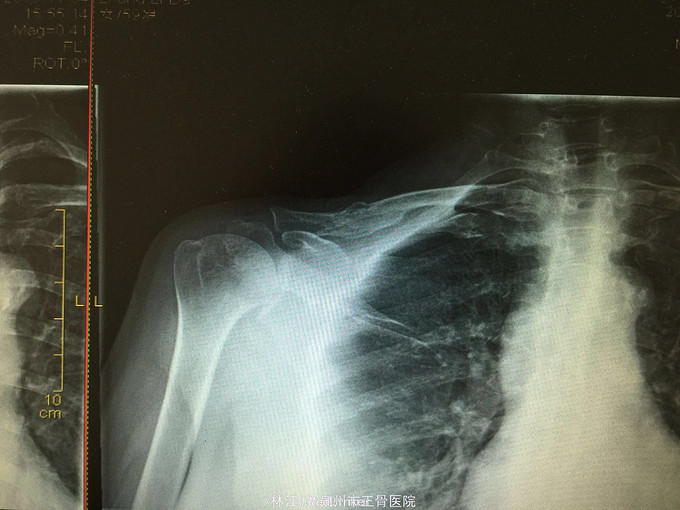

右锁骨粉碎性骨折闭合复位克氏针内固定术

摔伤致右肩部肿痛活动受限3小时

右锁骨部肿胀,锁骨中段压痛明显,可及明显骨擦感,右肩活动受限,肢端感觉活动正常

右锁骨粉碎性骨折 行闭合复位克氏针内固定术